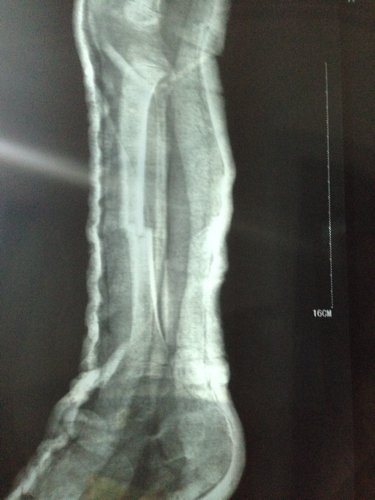

男孩三周岁 5-9 被电动车撞,右小腿胫骨骨折,正位对线良好,侧位错位三分之一。现差不多六周,前两天腿甩痛了就近急诊拍片,医生说骨头在长的,一周后把石膏拆掉吧,否则肌肉萎缩影响走路的,请各位医生指点一下,错位情况下,石膏拆了会影响恢复吗?因为两段骨头没合上阿,我上传一张之前的片子,请大家帮忙看一下。